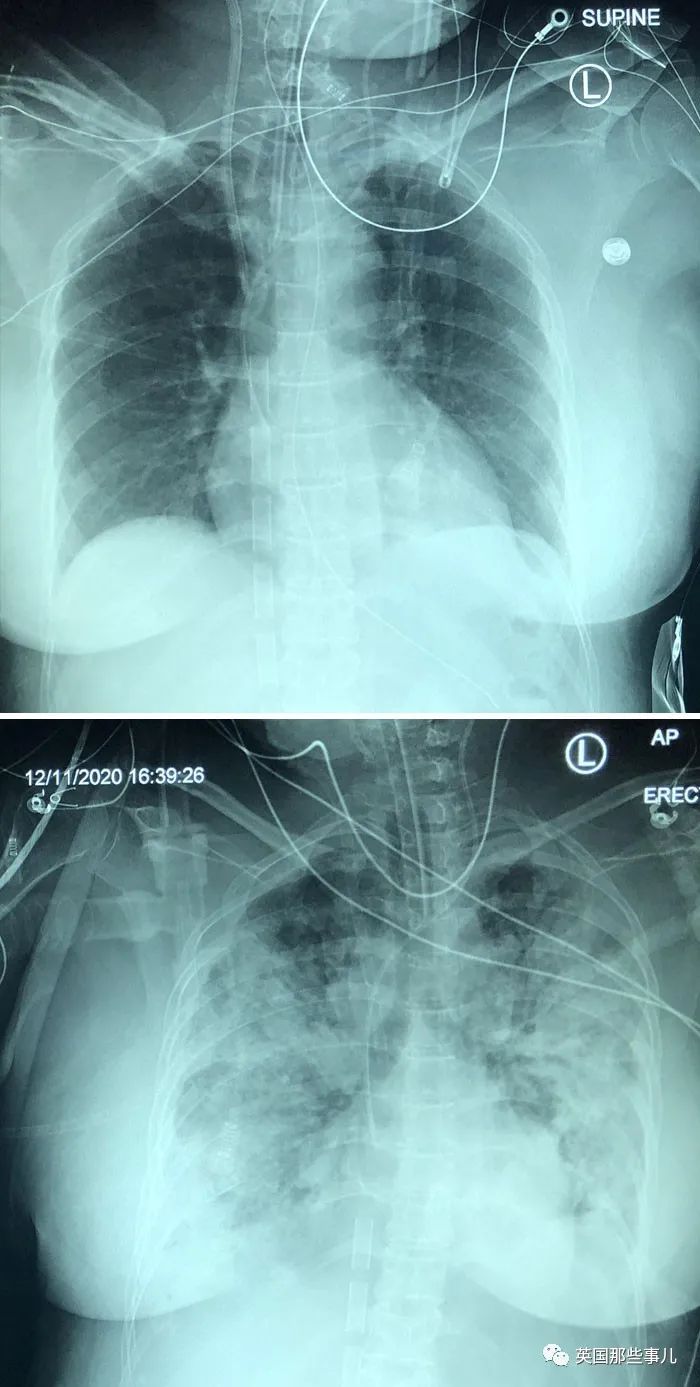

感染新冠肺炎五天後

靜脈注射水銀自殺未遂後,胸部變成了這樣....